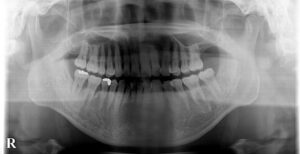

治療に先立ち

でっ歯さんの度合いを判定する

セファロというレントゲン撮影

お口のスキャナー

トリウスで歯並びをスキャン

パノラマというレントゲンも撮影

この精密検査のデータをもとに

松岡先生が治療を計画